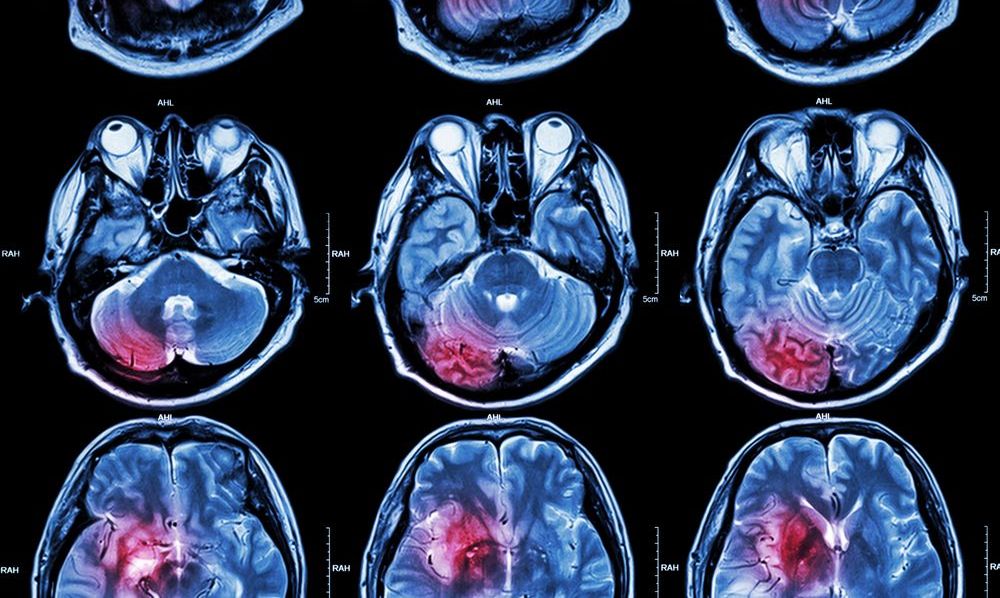

Investigan relación de derrames cerebrales con COVID-19.

Investigan relación de derrames cerebrales con COVID-19. Crédito: Shutterstock

Estos derrames, provocados por la generación de múltiples coágulos de sangre en arterias, venas, cerebro y otras partes centrales del organismo, han superado las especulaciones primigenias de que el virus únicamente afectaba el funcionamiento pulmonar y sugieren que se está lidiando con un enemigo mucho más formidable.

Ahora, los infartos cerebrovasculares, interrupciones repentinas del suministro de sangre, constituyen una de las más recientes relaciones que se han establecido con los efectos que el nuevo coronavirus produce al interior de los sistemas que invade. El estudio y la observación de esta correspondencia, señalan especialistas en salud, puede dar luz a interrogantes que ni siquiera se había considerado plantear.

Los análisis que se han llevado a cabo hasta el momento sugieren que los enfermos de Covid-19 pueden ser propensos a experimentar derrames cerebrovasculares bastante severos, capaces de destruir partes del cerebro responsables del movimiento y el habla.